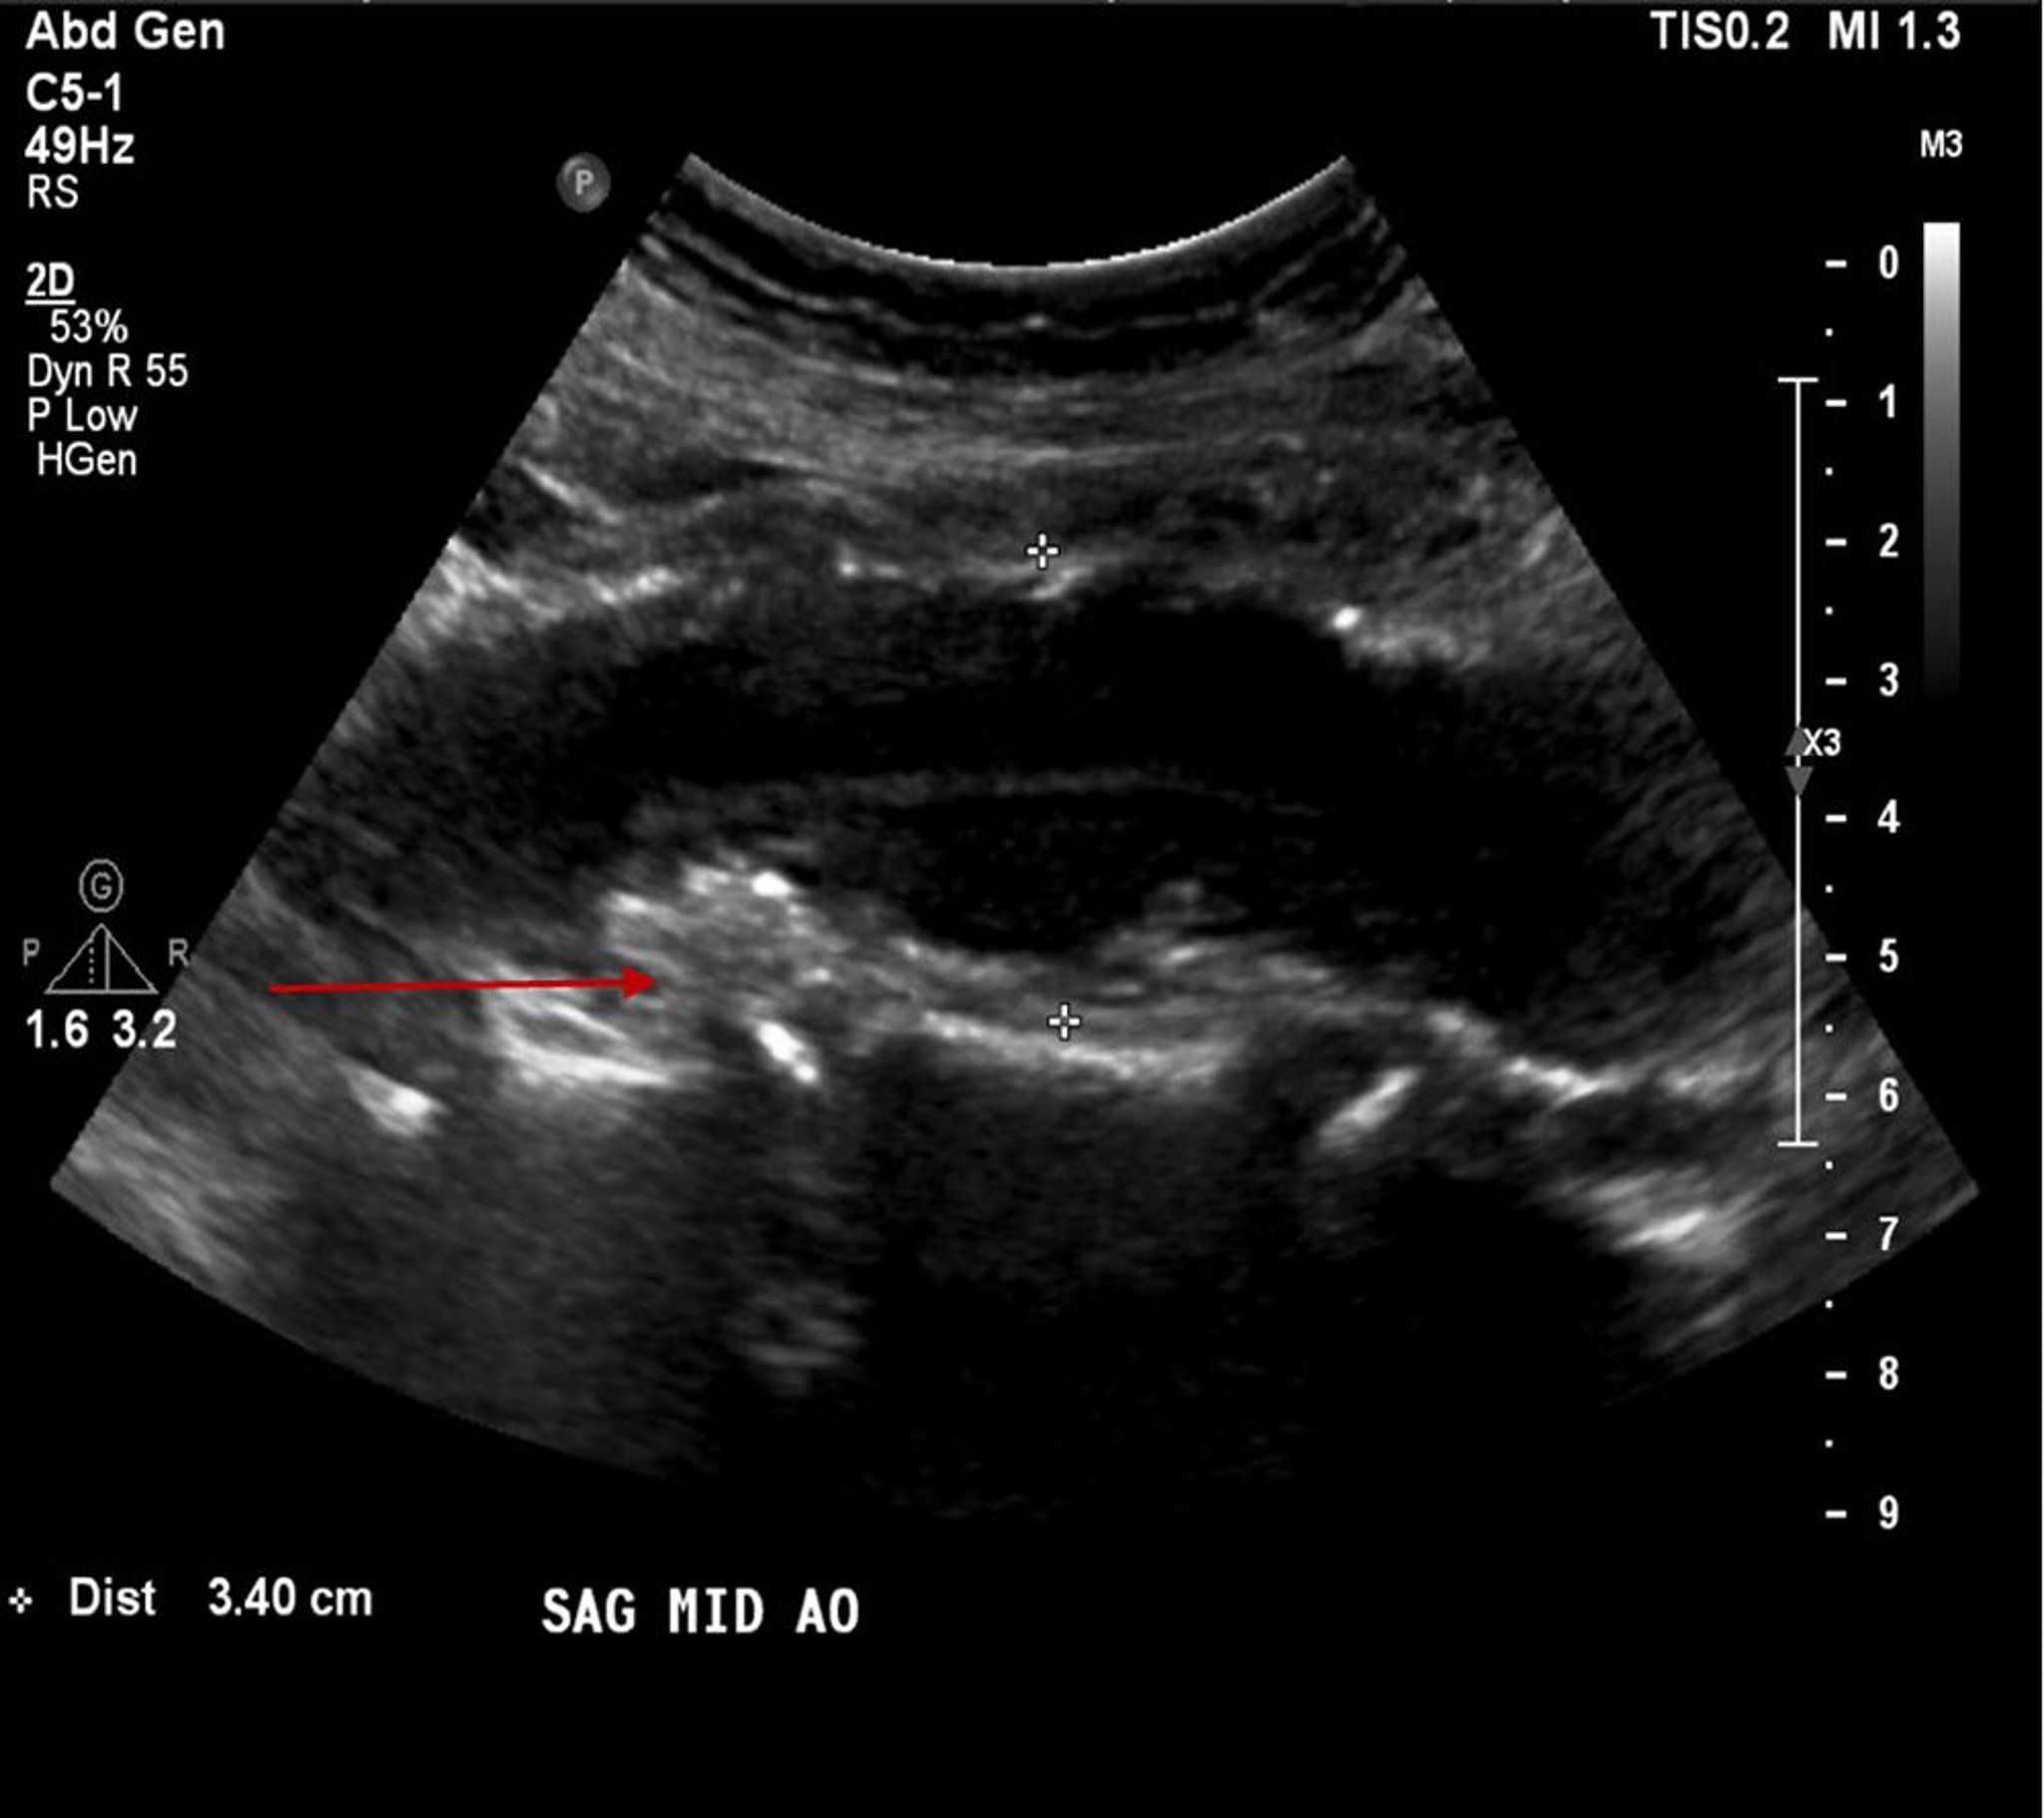

Abdominal Aortic Aneurysm (Ultrasound)

This patient has an abdominal aortic aneurysm measuring 3.4 cm (between the white crosses) as well as atherosclerotic plaque or mural thrombus (red arrow).